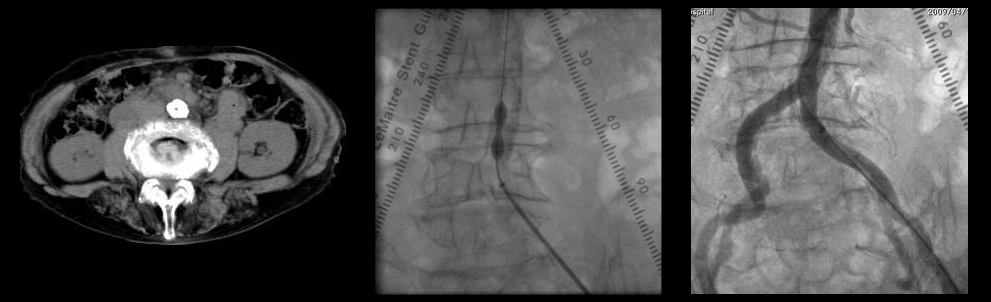

ガイドワイヤー通過

バルーン拡張

ステント留置

血管内手術

- 腸骨動脈狭窄 【写真】

- 浅大腿動脈狭窄 【写真】

考え方としては、早期であるほど2の血管内手術のみで治る可能性が高いと考えてよいでしょう。現在の末梢動脈に対する血管内手術の適応は、大動脈・腸骨動脈領域から膝下動脈、さらに足関節から足趾にまで及びます。しかし、それぞれの治療法には当然ながら適応があります。このためしばしば従来からの手術との組み合わせであるハイブリッド手術が必要になりますが、血管内呪術の関与する割合は8~9割にも及んでいます。